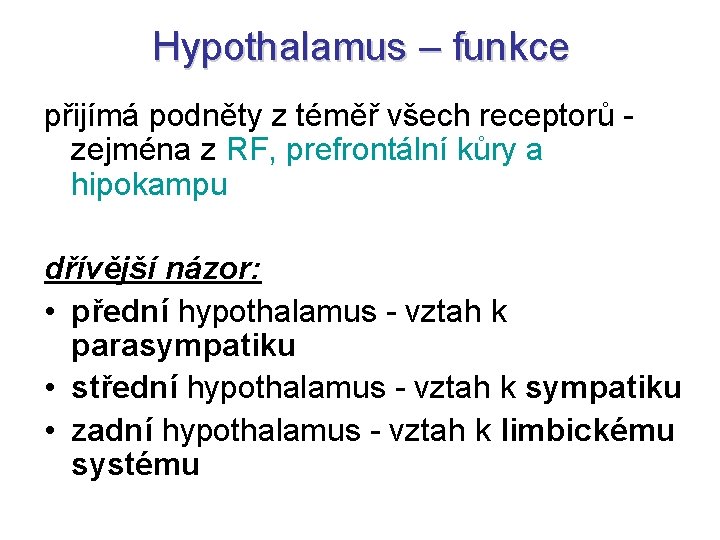

Hypothalamus – funkce přijímá podněty z téměř všech receptorů - zejména z RF, prefrontální kůry a hipokampu dřívější názor: • přední hypothalamus - vztah k parasympatiku • střední hypothalamus - vztah k sympatiku • zadní hypothalamus - vztah k limbickému systému